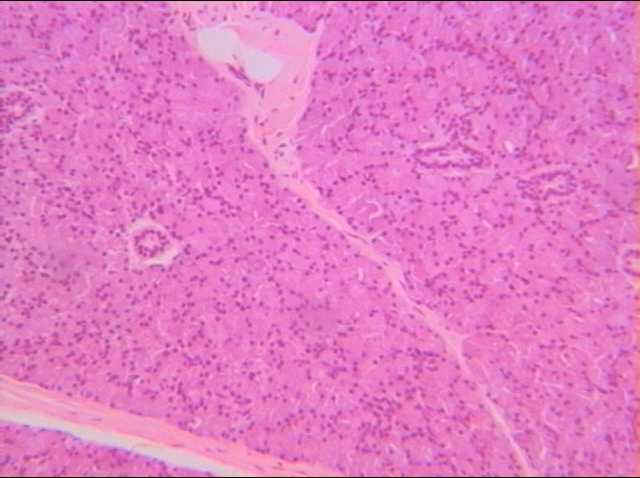

切片位置:唾腺(腮腺)(parotid gland)

切片倍率:100x

染色方式:h&e stain

此為腮線之組織切片,低倍觀察時可見由結締組織將腮腺區分為小區塊,稱為小葉。其小葉內主要構造為分泌唾液的腺泡及輸送分泌物的分泌管。